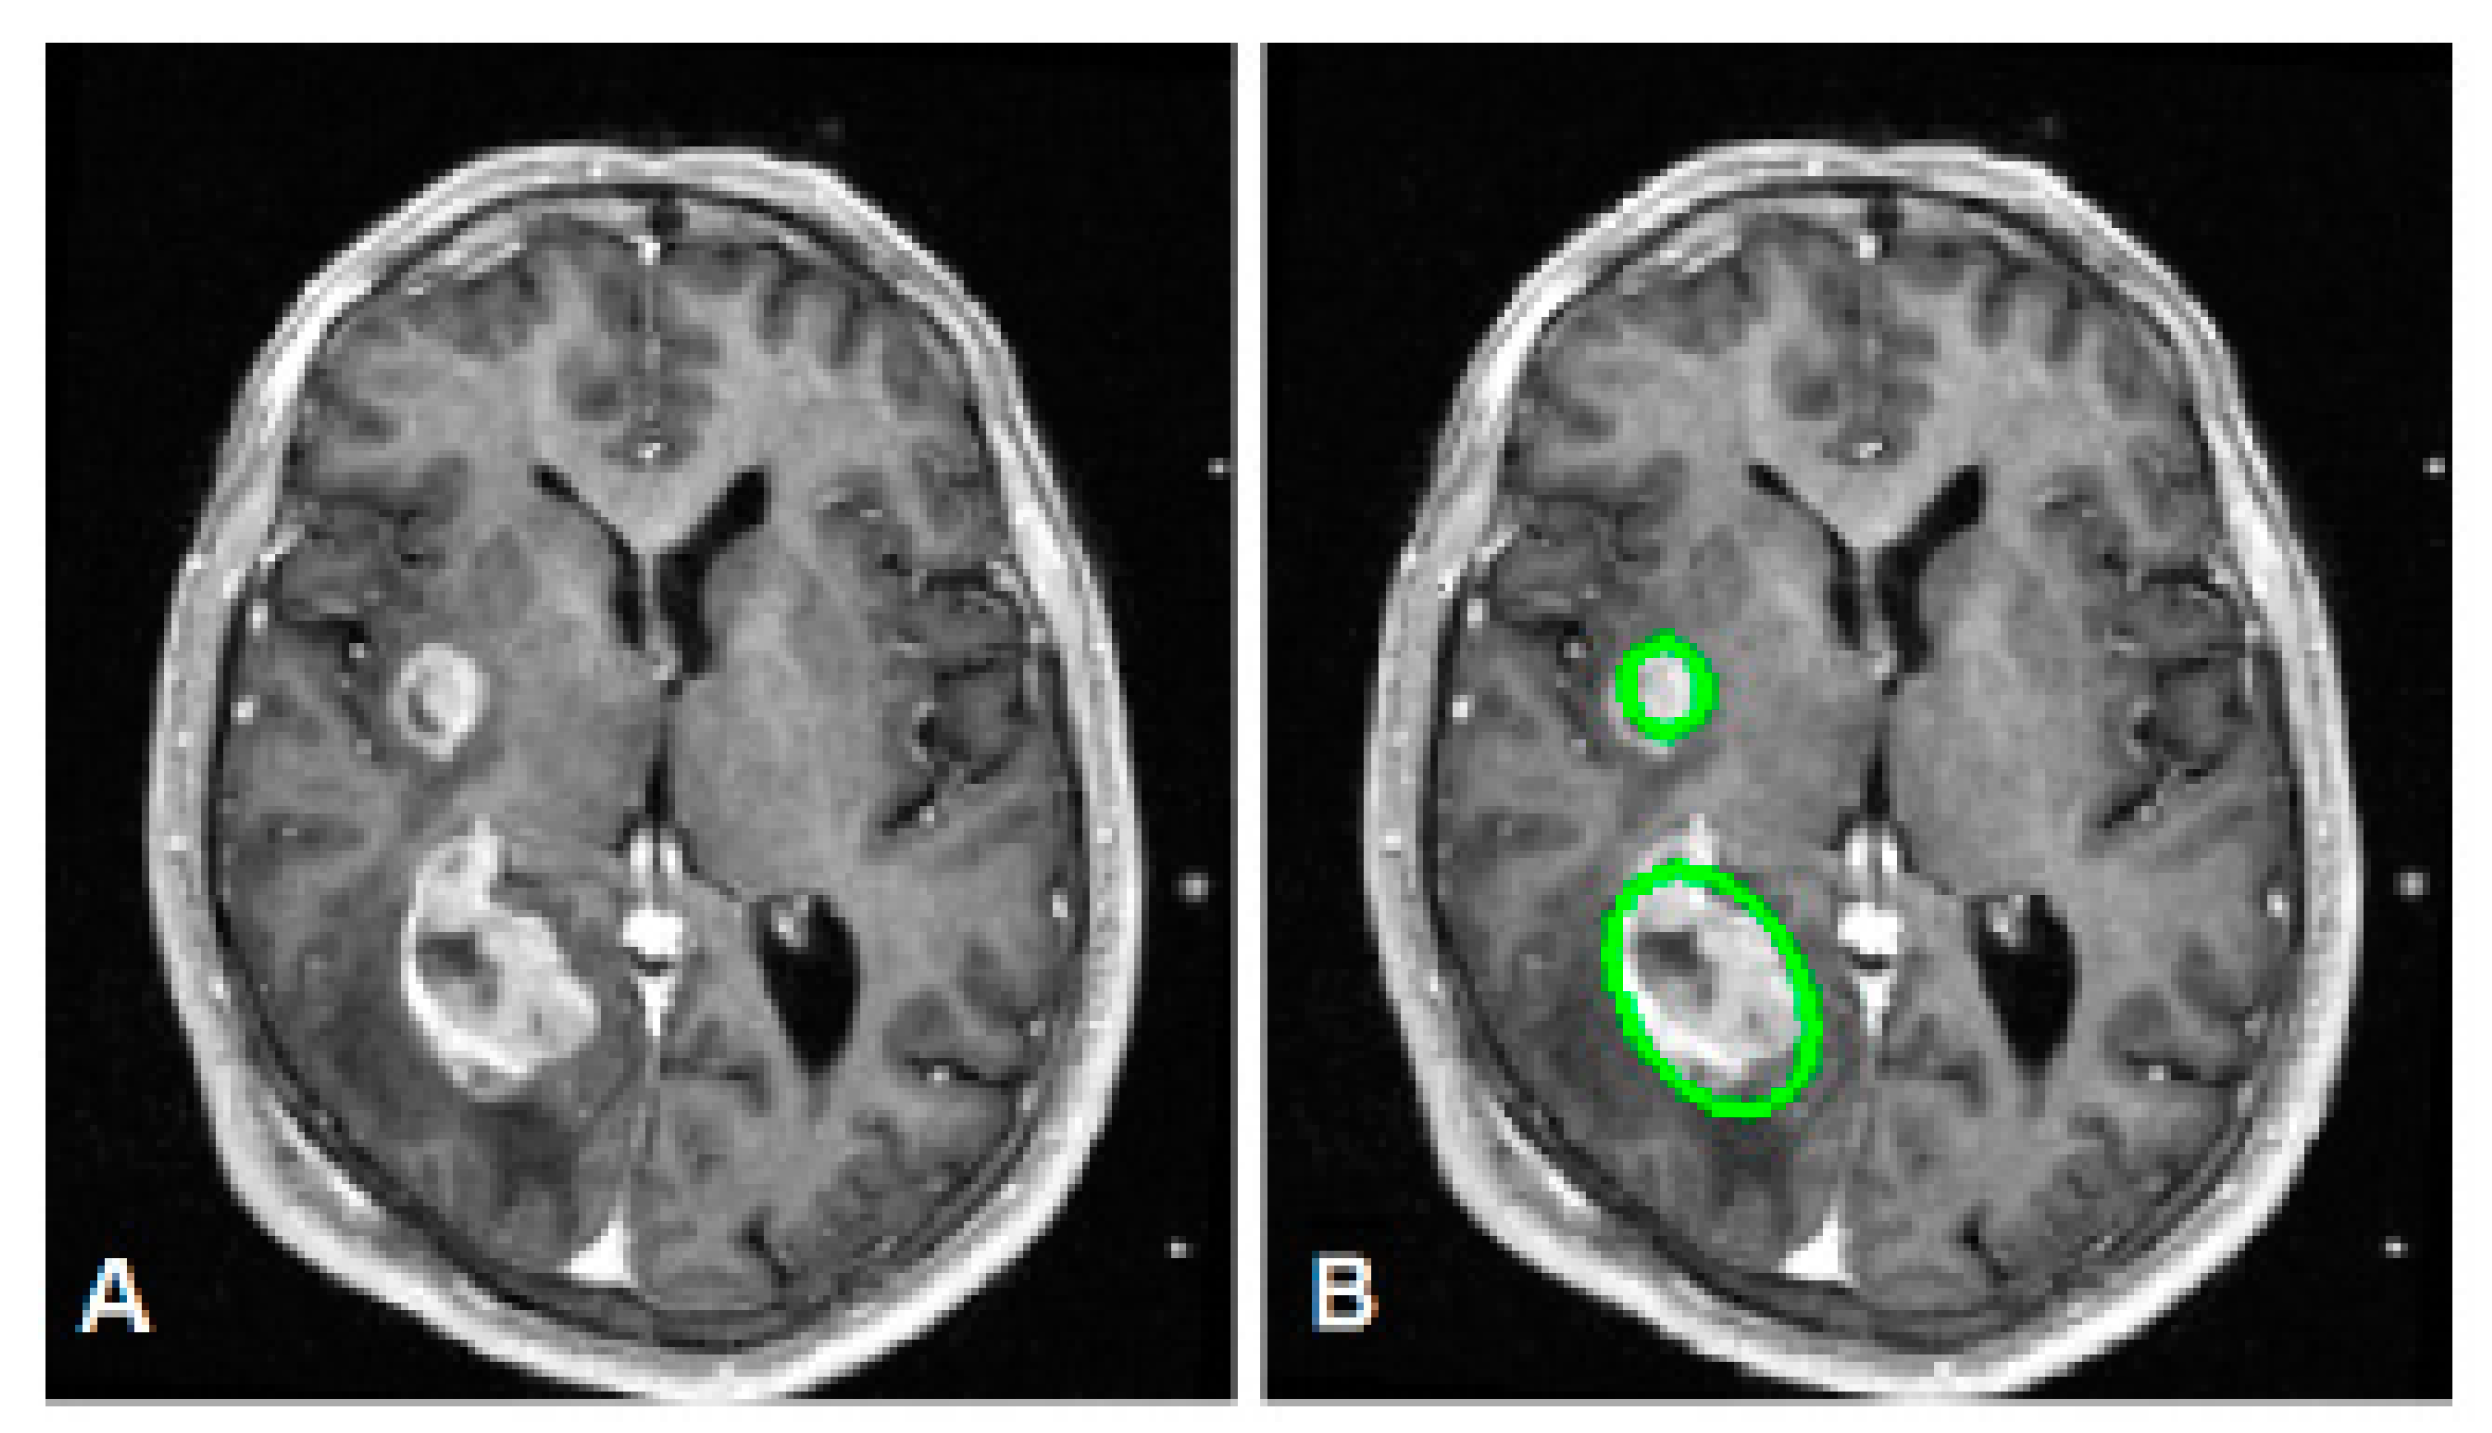

- Khalil, H.; Darwish, S.; Ibrahim, Y.; Hassan, O. 3D-MRI brain tumor detection model using modified version of level set segmentation based on dragonfly algorithm. Symmetry 2020, 12, 1256. [Google Scholar] [CrossRef]